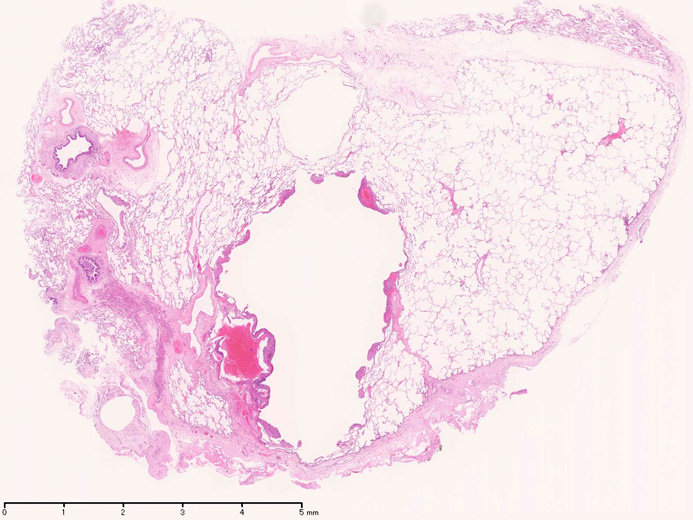

臨床的には進行性肺嚢胞化, くり返す肺気腫, 乳び性胸水貯留が特徴で, 多くの症例では進行性に呼吸不全となる*1

LAM患者さんに認められた両側肺気腫(右図:胸部CT)

初診時CT(左)から2年後のCTでは肺の嚢胞化が著明となっている。